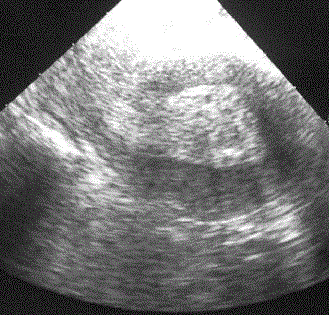

- 1) Ультразвуковая диагностика

Ультразвуковыми критериями гиперплазии являются следующие:

- 1) Увеличение толщины эндометрия более 10 мм

- 2) Неравномерность контура

- 3) При атипической гиперплазии наблюдается обильный кровоток в слизистой оболочке матке (неатипическая гиперплазия характеризуется слабой васкуляризацией).